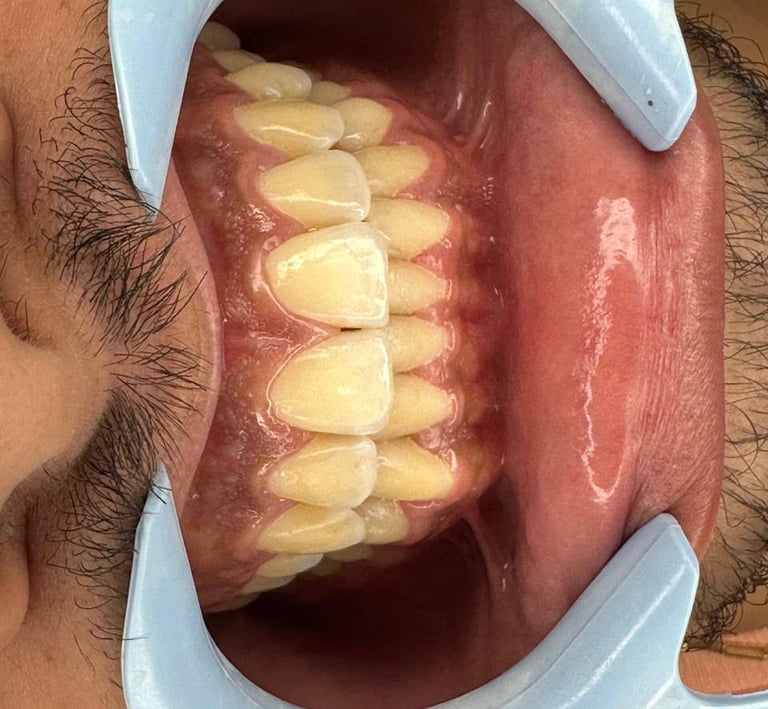

Aparelhos ortodônticos

Os aparelhos ortodônticos corrigem e

alinham os dentes. Além dos métodos

metálicos tradicionais, os aparelhos invisíveis

(como o Invisalign ) são discretos e práticos,

proporcionando um sorriso alinhado de forma

confortável e estética.